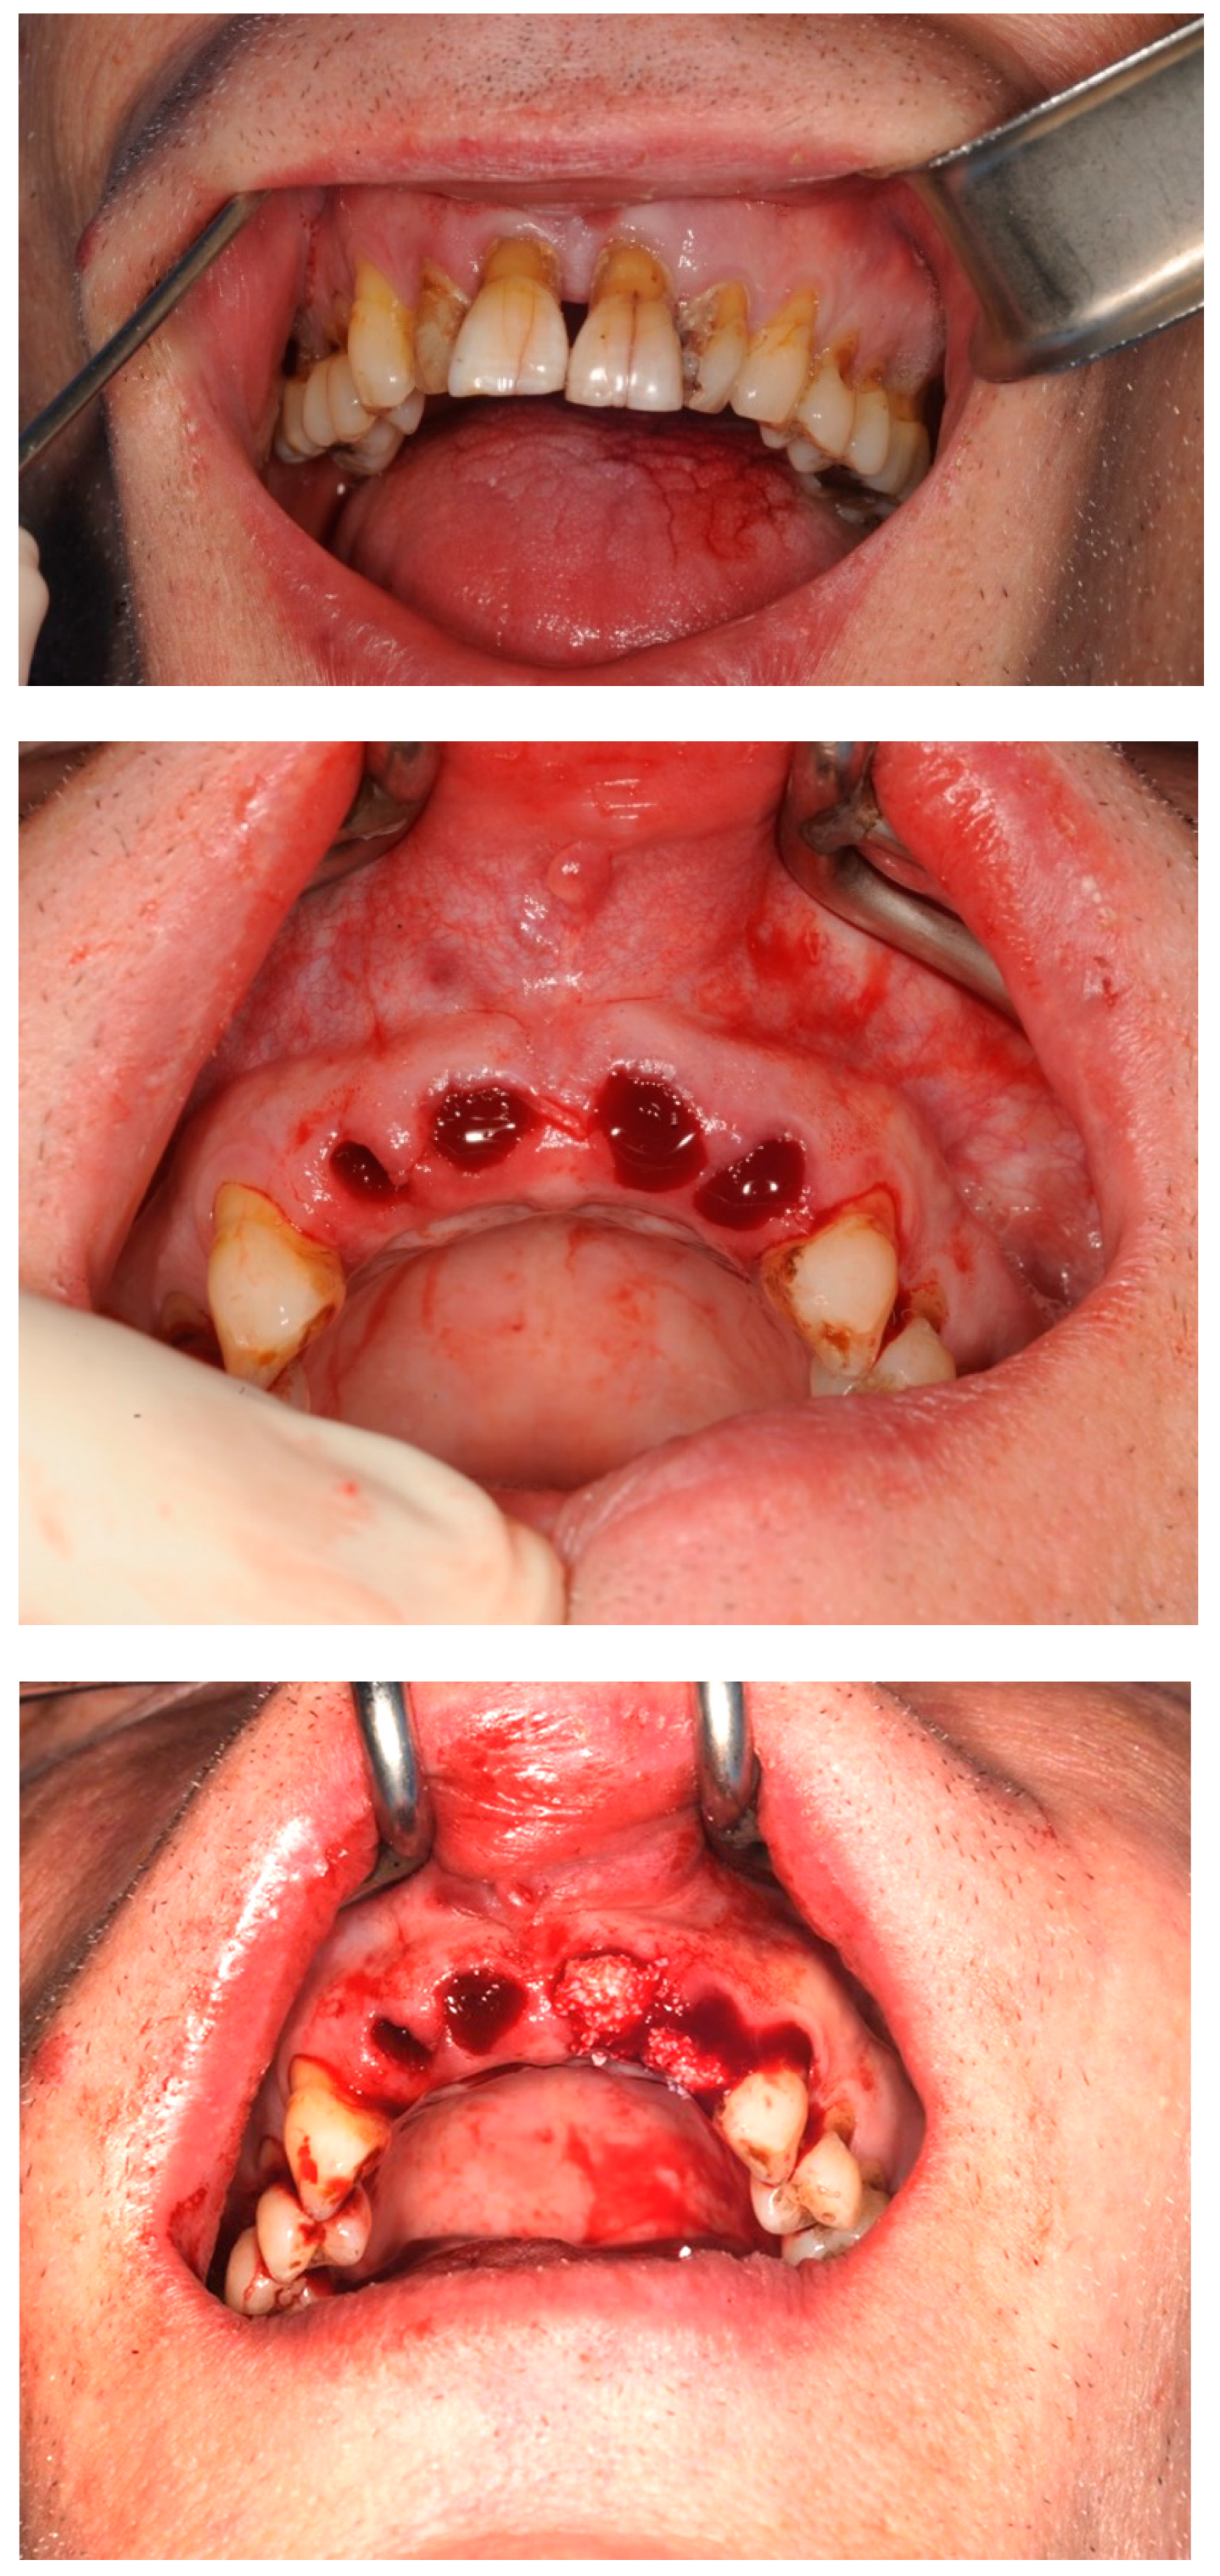

3.1. Case Study 1

3.2. Case Study 2

- Step 3: Teeth were removed using a minimally invasive extraction technique and the sockets were grafted with a xenograft and PRF

2.2. Alveolar Ridge Preservation Technique

| Case 1 | 60, male, prediabetes, non-smoker with no medication | open ARP | Full contour preserved | excellent | high | D2-3 | None | 8 weeks | 6 weeks | No crestal bone loss |

| Case 2 (implant 1) | 55, female, hay fever, non-smoker | open ARP | Full contour preserved | excellent | high | D2-4 | None | 9 weeks | 7 weeks | No crestal bone loss |

| Case 2 (implant 2) | 55, female, hay fever, non-smoker | open ARP | Full contour preserved | excellent | high | D2-4 | None | 9 weeks | 8 weeks | No crestal bone loss |